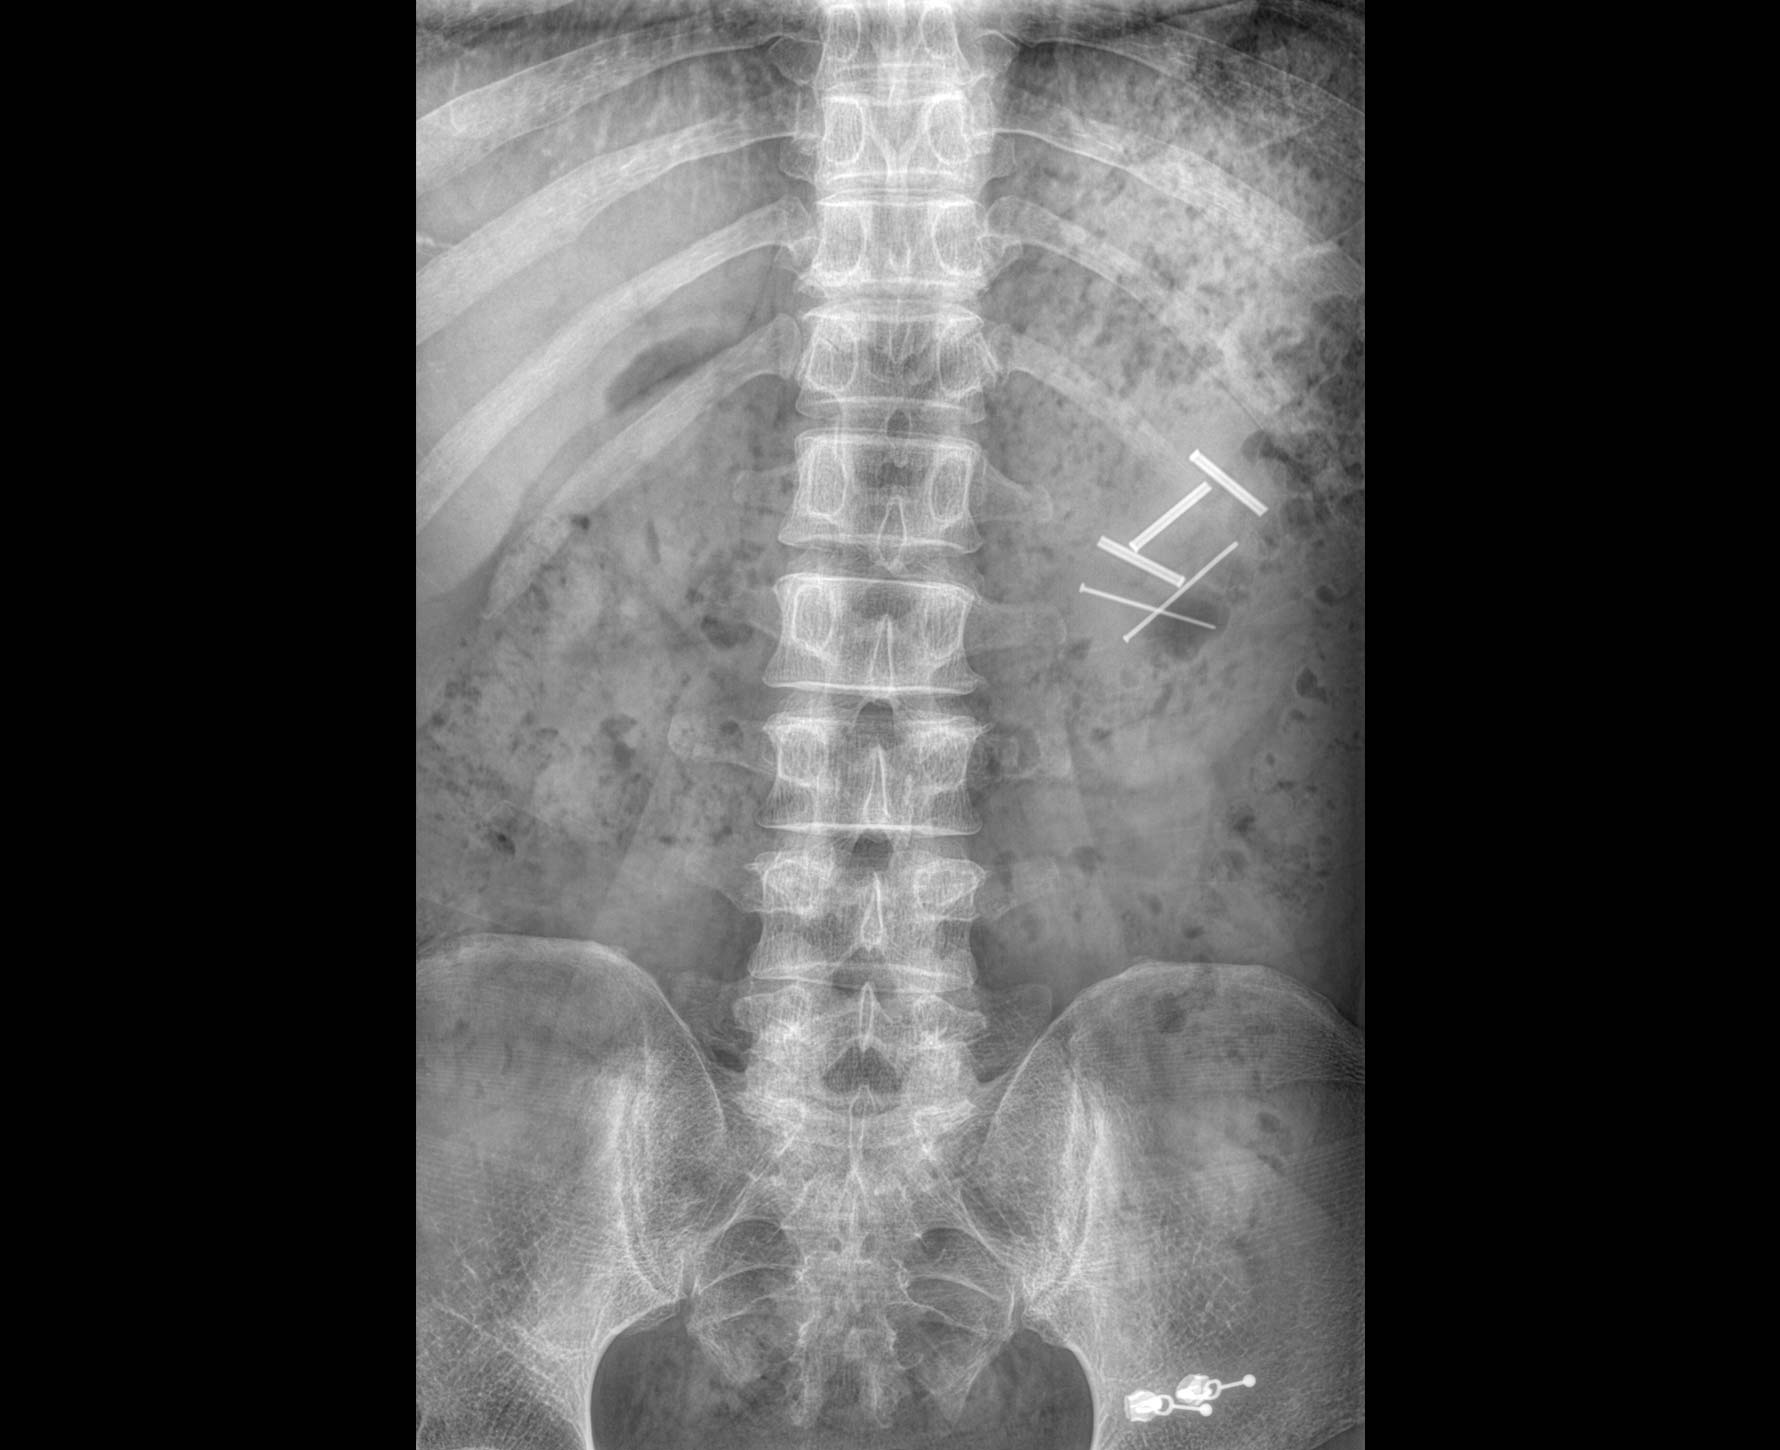

無縫融合處理,保證高質量全景影像。